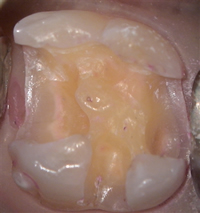

当院では、2,004年に歯科用顕微鏡OPMI PICOを導入しました。写真は顕微鏡で撮影した虫歯除去後の歯の写真です。

顕微鏡歯科(顕微鏡下で行われる歯科治療)では、拡大された鏡像をわずか数十〜数百ミクロンの精度で行う治療になります。